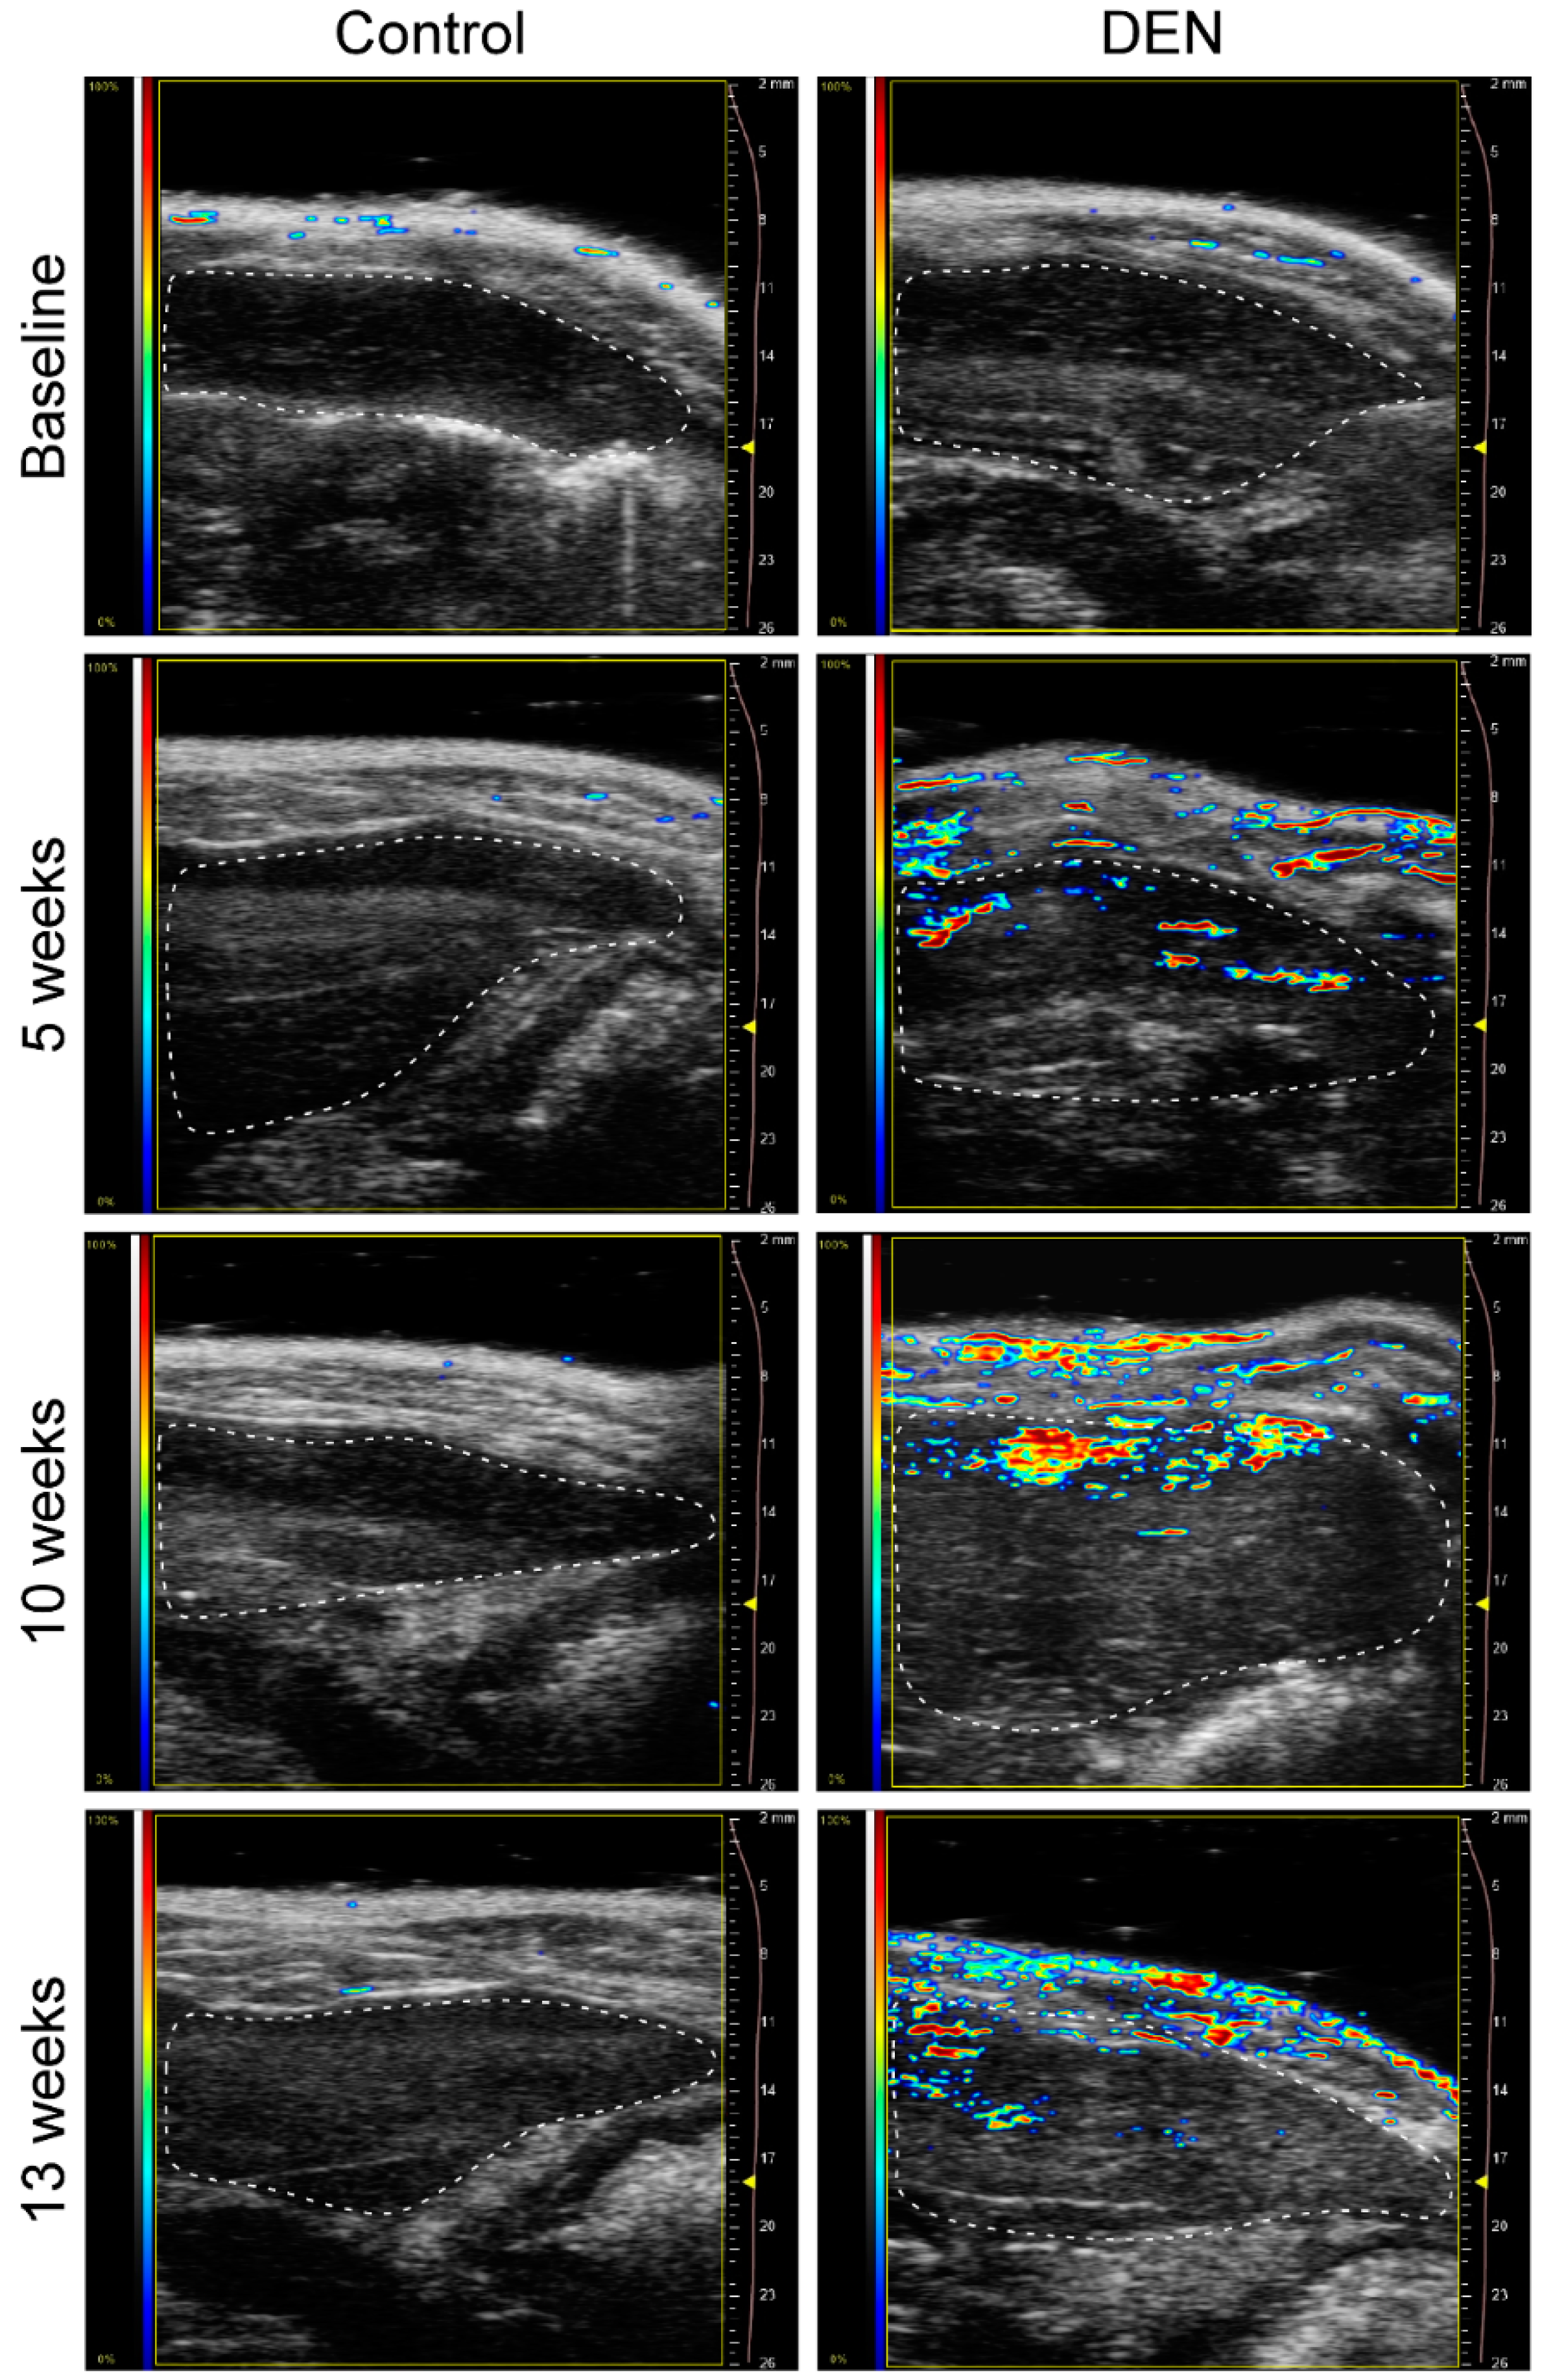

3.2. Sonographic Imaging of Liver Tissue and Assessment of Texture Features

3.3. Sonographic Imaging of Hepatorenal Interface and Assessment of HRI